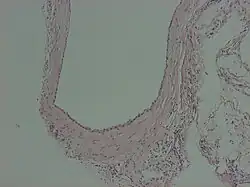

A peritoneal inclusion cyst is a cyst-like structure that appears in the pelvis due to non neoplastic reactive mesothelial proliferation, often as a consequence of prior episodes of pelvic inflammation, as can occur in pelvic inflammatory disease. It has the potential to mimic ovarian cysts, hydrosalpinx or even malignancy, due to its nonspecific anechoic appearance.[1]